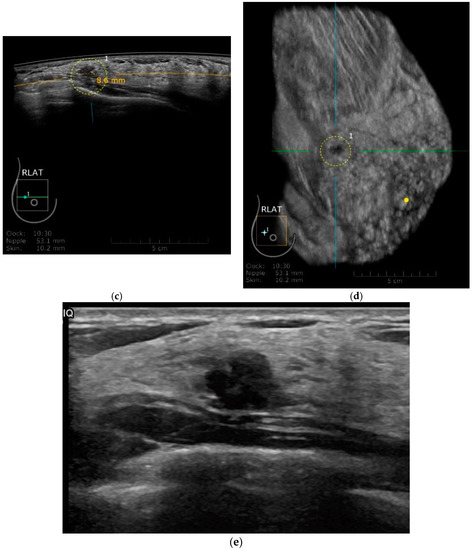

Breast Ultrasound Images For A 46 Year Old Woman With An Invasive Download Scientific Diagram

Benign And Malignant Tumors A And B Were Obtained From Breast Download Scientific Diagram

Sample Images Of Breast Ultrasound Images Of Different Cases In The Two Download Scientific Diagram

A A Simple Breast Cyst 75 B Breast Ultrasound Showing A Cancer Download Scientific Diagram